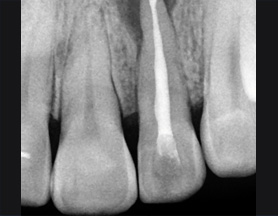

기존 신경치료는 양호한 상태이나 치근부위에

염증과 치조골 소실이 진행 중

치아 뿌리 쪽 잇몸을 절개하고 치조골 부위의

염증조직을 제거.(난이도 중)